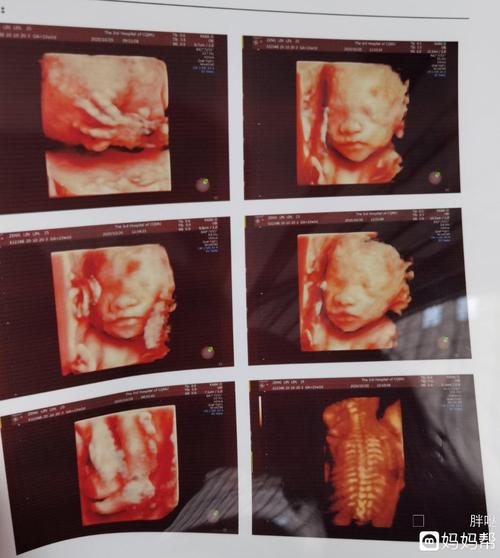

胎儿鼻骨缺失和或发育不良的医生专业指导

今天照了四维医生说鼻骨未见为娘很是担

宝宝没有鼻骨,会不会是畸形

有没有跟我一样的宝妈,胎儿鼻骨及颌骨扁平